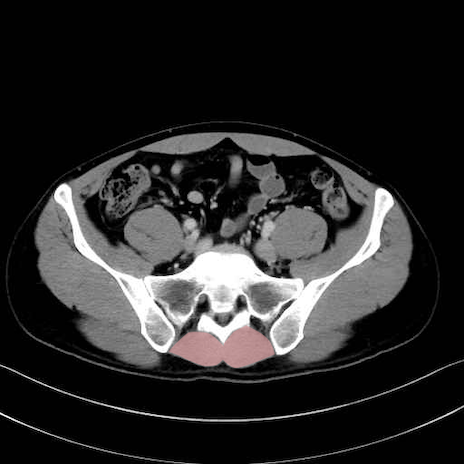

肛門挙筋 (Levator ani)